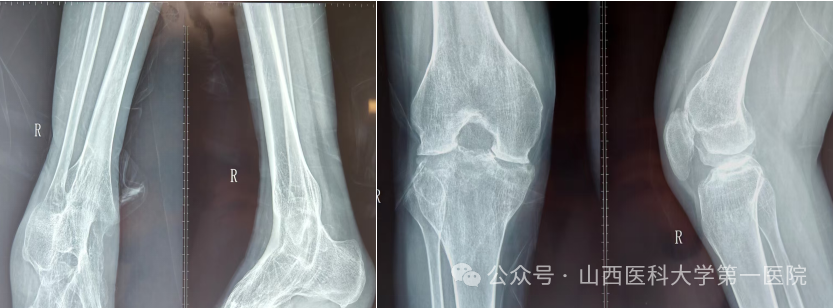

一名42岁的强直性脊柱炎患者,多年来饱受病痛折磨。随着病情进展,双侧髋关节逐渐“锈死”,无法弯腰、下蹲,甚至连坐下都成了奢望——吃饭只能站着,休息只能躺着,生活自理能力几乎丧失。接诊后,骨科杨自权主任团队对患者进行全面检查,发现患者不仅脊柱强直呈“板状腰”,双侧髋关节出现严重融合,而且双膝、双踝关节功能明显下降,手术难度极大。

针对患者复杂病情,科室组织多学科讨论。为实现从“站坐难安”到“稳步前行”,杨自权主任团队决定先为患者实施“右侧人工全髋关节置换术”。术中,团队凭借精湛技术,精准处理强直融合的关节结构,在保护周围神经血管的同时,成功植入新的人工关节假体。